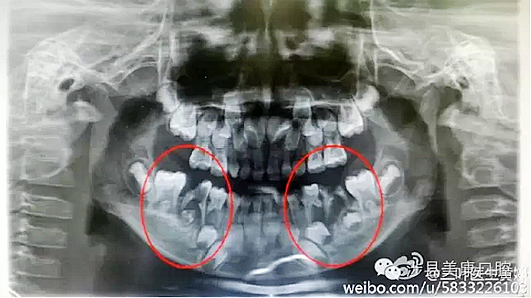

普通家長(zhǎng)看了這張牙片估計(jì)能看出來(lái)孩子的牙不好,但是究竟不好到什么程度呢,讓葉子姐告訴大家:

上圖孩子的乳牙感染已經(jīng)將下面骨感染到吸收消失,并且直接影響到了下面的恒牙胚,家長(zhǎng)們上點(diǎn)心吧。那些說(shuō)乳牙不用治療,換牙就會(huì)好的人(包括醫(yī)生)還是睜開眼睛看看吧,不要自欺欺人,更不要用自己的錯(cuò)誤誤導(dǎo)他人誤導(dǎo)大眾。

網(wǎng)友又不明白了,什么叫吸收消失?看x片看不懂哎......

黑色部分表示那里的骨頭感染已經(jīng)爛沒(méi)有了,消失了,牙胚應(yīng)該在健康頜骨里孕育生長(zhǎng)發(fā)育,現(xiàn)在在感染的病灶里生長(zhǎng),在膿水里侵泡。

又有好奇網(wǎng)友問(wèn)他怎么有那么多牙?

乳牙下面有恒牙孕育著。